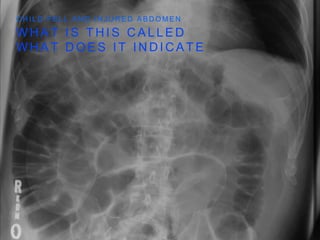

M E A N S F R E E A I R I N P E R I T O N E A L

C A V I T Y

F R E E A I R U N D E R D I A P H R A G M

W H A T I S T H I S C A L L E D

W H A T D O E S I T I N D I C A T E

C H I L D F E L L A N D I N J U R E D A B D O M E N

D O U B L E W A L L

S I G N

• AIR IS PRESENT ON

BOTH SIDES OF THE

INTESTINAL WALL

• INDICATES FREE AIR IN

THE PERITONEAL

CAVITY

M E AN S F R E E A I R I N P E R I T O N E A L C A V I T Y F R E E A I R U N D E R D I A P H R A G M

W H AT I S T H I S C A L L E D W H A T D O E S I T I N D I C A T E C H I L D F E L L A N D I N J U R E D A B D O M E N

D O UB L E W A L L S I G N • AIR IS PRESENT ON BOTH SIDES OF THE INTESTINAL WALL • INDICATES FREE AIR IN THE PERITONEAL CAVITY